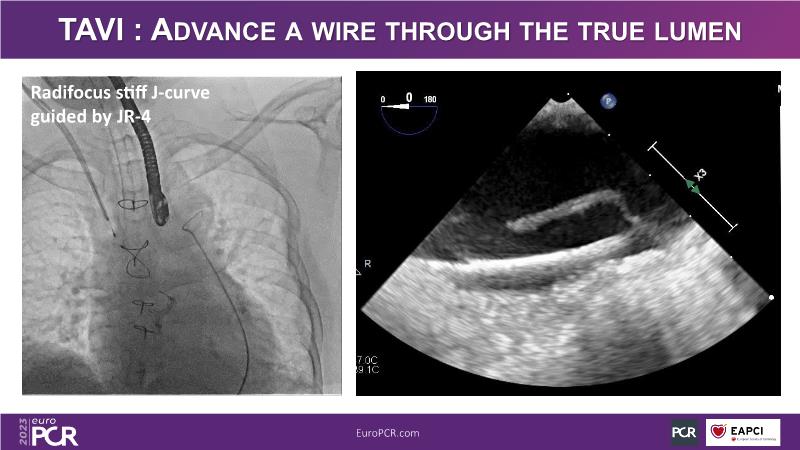

In this session, watch the case of a 56-year-old man with HTN, DM, stable CAD, PFO and previous ischaemic stroke, who presented with severely calcified CTO lesion on proximal LAD and significant mid-RCA lesion, and find out how he was treated LIVE... among others!